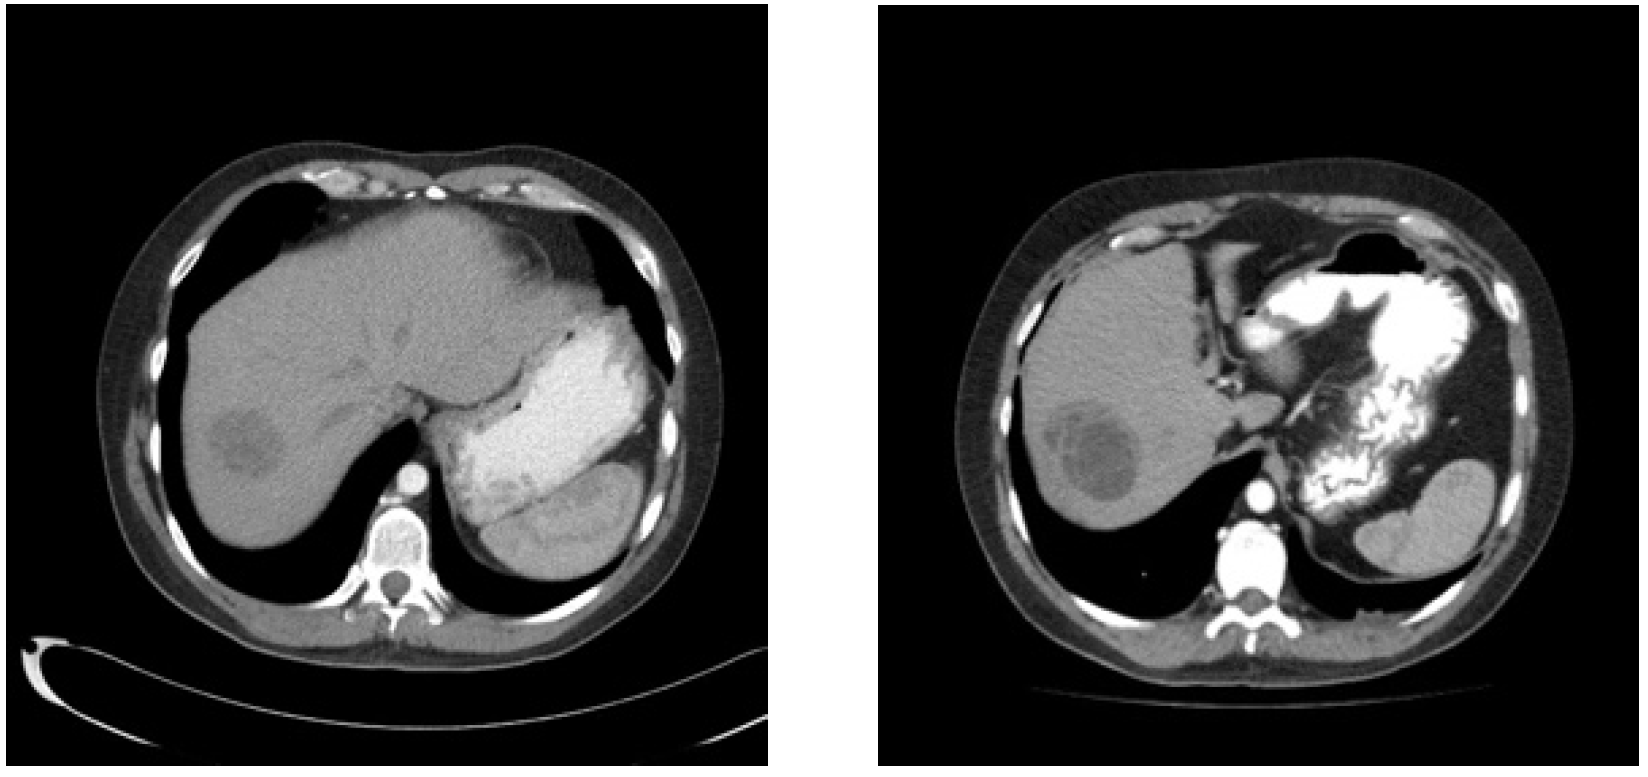

Nineteen months from diagnosis, the largest liver lesion demonstrated growth on imaging; however, tumor markers remained normal (Figure 3). Resection of this large lesion in segment 7, as well as a wedge resection of a smaller lesion in segment 8, was performed. Pathology revealed mature teratoma in both the 5.5 cm and 0.8 cm lesions.

Figure 3. From left to right, Post-chemotherapy unenhanced CT Scan showing improvement in liver metastases and 18 month follow up enhanced CT scan showing enlarging dominant liver metastases.